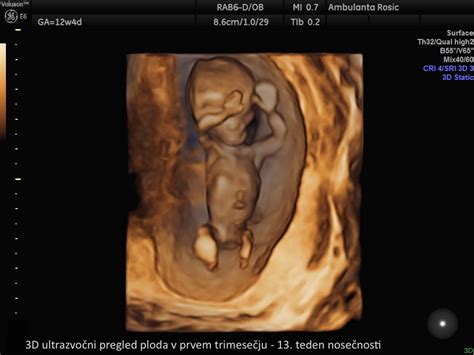

V prvem trimesečju (do 13. tedna) se opravijo ključni pregledi, vključno z laboratorijskimi analizami krvne slike, krvne skupine, Rh faktorja, testom na toksoplazmo in sifilis ter ultrazvočno potrditvijo nosečnosti. Med 11. in 14. tednom se priporoča merjenje nuhalne svetline, ki v kombinaciji z merami ploda in materinim starostjo omogoča oceno tveganja za kromosomske nepravilnosti.

Prvo trimesečje | 3D animirani vodnik za nosečnost